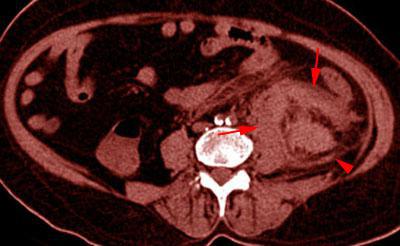

Aunque la ecografía abdominal permite identificar la gravedad de la lesión, la prueba de elección es el AngioTC de aorta abdominal en fases arterial y venosa que permitirá diagnósticar la integridad del pedículo vascular y la asociación de otras lesiones abdominales de origen traumático.

La técnica de UroTC puede ser muy útil cuando se sospeche la afectación de la vía urinaria.